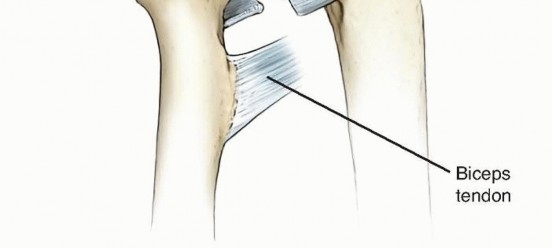

FIG 2 • Ligamentous anatomy of the proximal radioulnar joint. The annular ligament is the principal stabilizer of the radial head during forearm rotation. In supination, the annular and quadrate ligaments are taught and increase stability of the proximal radioulnar joint.